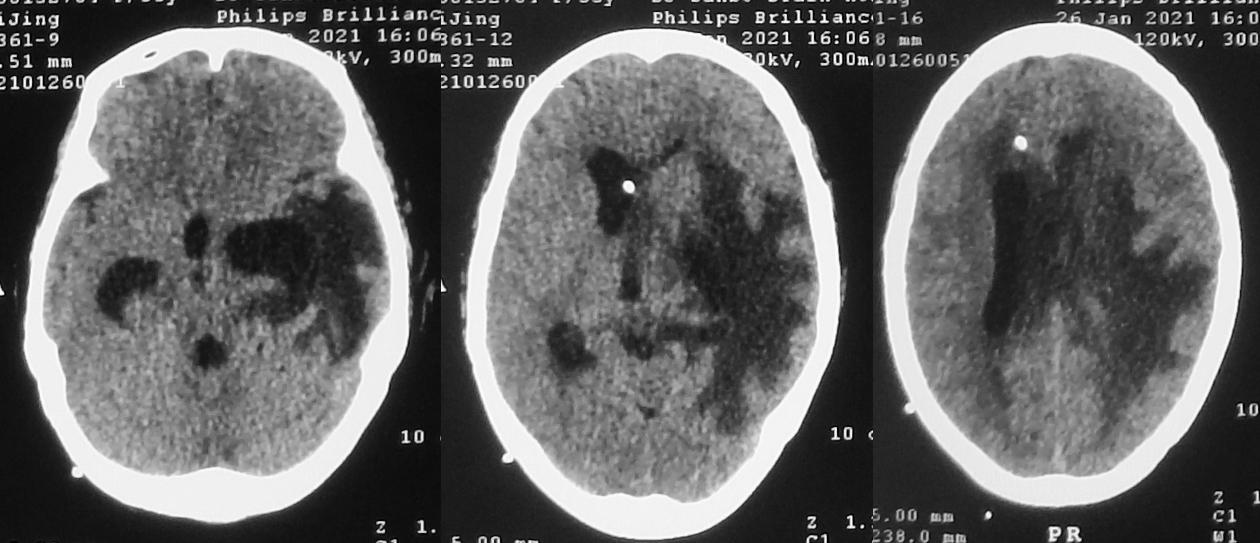

入院当天复查头CT见右侧脑室额角内分流管,脑室扩张;左侧颞角可见外引流管( 图-32 )。

图-32: 2021年2月10日头CT

于入院当天行脑室腹腔分流管拔除+脑室外引流术,同时拔除了左颞角引流管。术后第2天即2021年2月12日,复查头颅CT见引流管位置满意,右侧脑室仍稍扩张( 图-33 )。患者病情平稳,无发热,神志模糊。

图-33: 2021年2月12日头CT

术后第8天,即2021年2月18日,复查头颅CT见右侧脑室缩小,左侧脑室稍扩张( 图-34 )。脑脊液细菌培养结果回报为表皮葡萄球菌,但患者无发热,神志逐渐好转,由入院时的刺痛睁眼好转为可自动睁眼,左侧肢体可遵嘱活动( 图-35 )。

图-34: 2021年2月18日头CT

发病后108天,入脑脊液科治疗14天,即2021年2月24日,患者病情稳定,无发热,脑脊液细菌培养阴性,提示颅内感染的表皮葡萄球菌得到控制。复查头颅CT见右侧脑室缩小,左侧脑室颞角较前无明显变化( 图-37 ),当天行右侧脑室腹壁外引流术。

图-37: 2021年2月24日头CT

脑室腹壁外引流术后第1天,即2021年2月25日,复查头颅CT见脑室系统缩小,左侧脑室颞角较前无明显变化,左侧脑室颞角及三角区周围仍明显水肿( 图-38 )。患者病情稳定,可遵嘱动作,但反应稍慢( 图-39 )。

图-38: 2021年2月25日头CT

患者病情稳定,神志清楚,但一直对言语反应慢,于发病后115天,入脑脊液科治疗21天,即2021年3月3日,复查头CT见左颞角仍呈稍扩张,左侧脑室颞角及三角区周围仍明显水肿( 图-40 )。

图-40: 2021年3月3日头CT

于2021年3月3日当天行左侧脑室颞角腹壁外引流术。左侧脑室颞角引流术后第1日,即2021年3月4日,复查头颅CT见左颞角缩小,颞角引流管位置满意( 图-41 )。

图-41: 2021年3月4日头CT